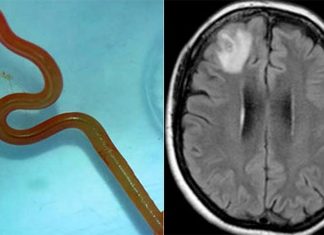

호주 의학 전문가들이 NSW 여성의 뇌 안에서 비단뱀(python snake)의 살아있는 8cm 길이의 회충을 발견했는데, 이는 세계 최초의 사례라고 9news가 전했다.